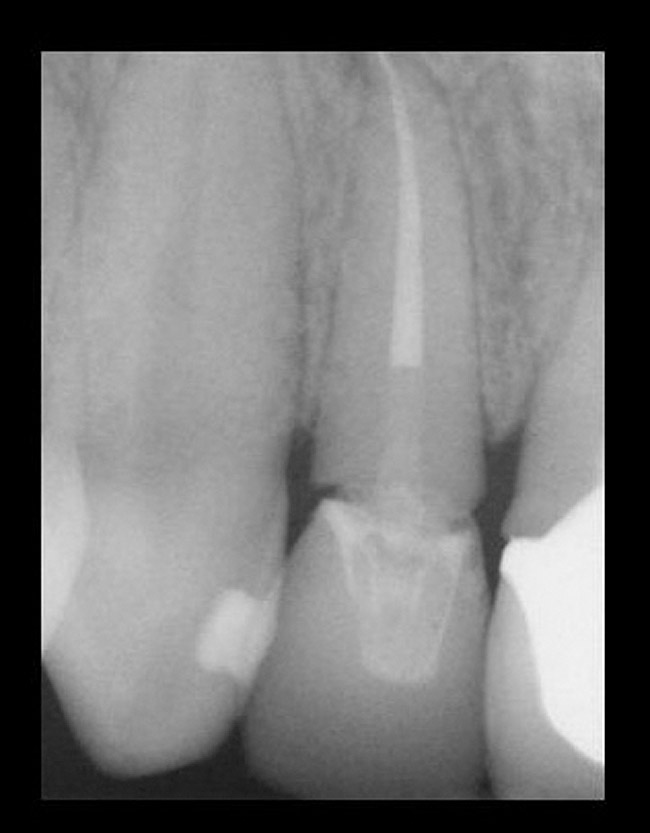

The decision to retain or extract a questionable tooth is one that occurs frequently in dental practice. There are many factors to consider when making this decision. Some situations are very straightforward (Figure 1) while others fall into a “gray” area of decision-making (Figure 2). This article will provide guidelines for determining whether to extract or retain a tooth when the decision is not so straightforward using structural, periodontal, endodontic, and esthetic criteria. Some teeth may involve only one of these areas, and some will involve various combinations of these areas. There are also other important factors to consider such as patient expectations, patient finances, and patient compliance, but these topics vary from patient to patient and should be discussed with each individual patient. While these topics are very important to the decision-making process, they are beyond the scope of this article.

A tooth that is deemed structurally restorable and periodontally sound that requires endodontic therapy has an overall success rate of 90%. There are certain conditions that lower the success rate of which the clinician needs to be aware. According to the Toronto Study,34 a longitudinal study, a vital tooth requiring initial therapy will have a success rate of 93%. A non-vital tooth with a periapical radiolucency < 5 mm will have a 89% success rate.34 A non-vital tooth with periapical radiolucency > 5 mm will have a 74% success rate.34 Clearly, a tooth with periapical radiolucency > 5 mm significantly decreases the success rate of endodontic therapy (Figure 12).